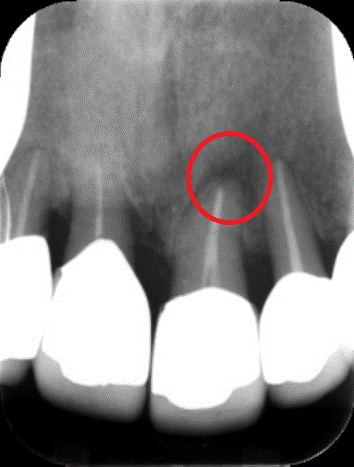

上記の画像は、「左」が3次元のCT画像で、「右」が2次元レントゲン画像です。左の赤丸がついている「黒い部分」が問題の箇所ですが、右の画像では黒く映っていません。CTであれば、はっきり確認できるため、治療すべき部位を見落とすリスクが下がります。